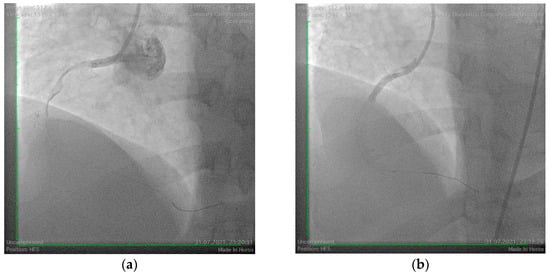

A 42-year-old male with cardiovascular risk factors, including smoking, grade I obesity, and dyslipidemia, presented to our clinic with an inferolateral ST-segment elevation myocardial infarction. The patient had no prior history of allergic reactions or significant personal or family medical history. However, detailed anamnesis revealed that symptoms began approximately one hour after the ingestion of a 1 g tablet of amoxicillin/clavulanic acid during a dental consultation. On clinical examination, the patient had a blood pressure of 130/100 mmHg, heart rate of 86 bpm, and oxygen saturation (SpO2) of 99%. Laboratory investigations demonstrated elevated myocardial enzymes (CK-MB = 128 U/L, LDH = 1390 U/L, AST = 175 U/L), marked dyslipidemia (non-HDL cholesterol = 201 mg/dL, LDL cholesterol = 145 mg/dL), and evidence of an inflammatory response (CRP = 105 mg/L, erythrocyte sedimentation rate = 46 mm/h, fibrinogen = 660 mg/dL). Echocardiography revealed a normal left ventricular ejection fraction (LVEF = 55%) with hypokinesia of the inferior and lateral walls. Coronary angiography showed an acute thrombotic occlusion of the proximal right coronary artery. The lesion was treated with percutaneous coronary angioplasty and the deployment of two drug-eluting stents (Figure 3). However, no reflow phenomena were observed during the procedure, necessitating the initiation of triple antithrombotic therapy, including aspirin (75 mg once daily), clopidogrel (75 mg once daily), and acenocoumarol with strict International Normalized Ratio (INR) monitoring for a limited duration.

Figure 3. Coronary angiography of the right coronary artery. (a) Acute thrombotic occlusion of the proximal right coronary artery; (b) Angiography aspect after revascularization with phenomena of no reflow.